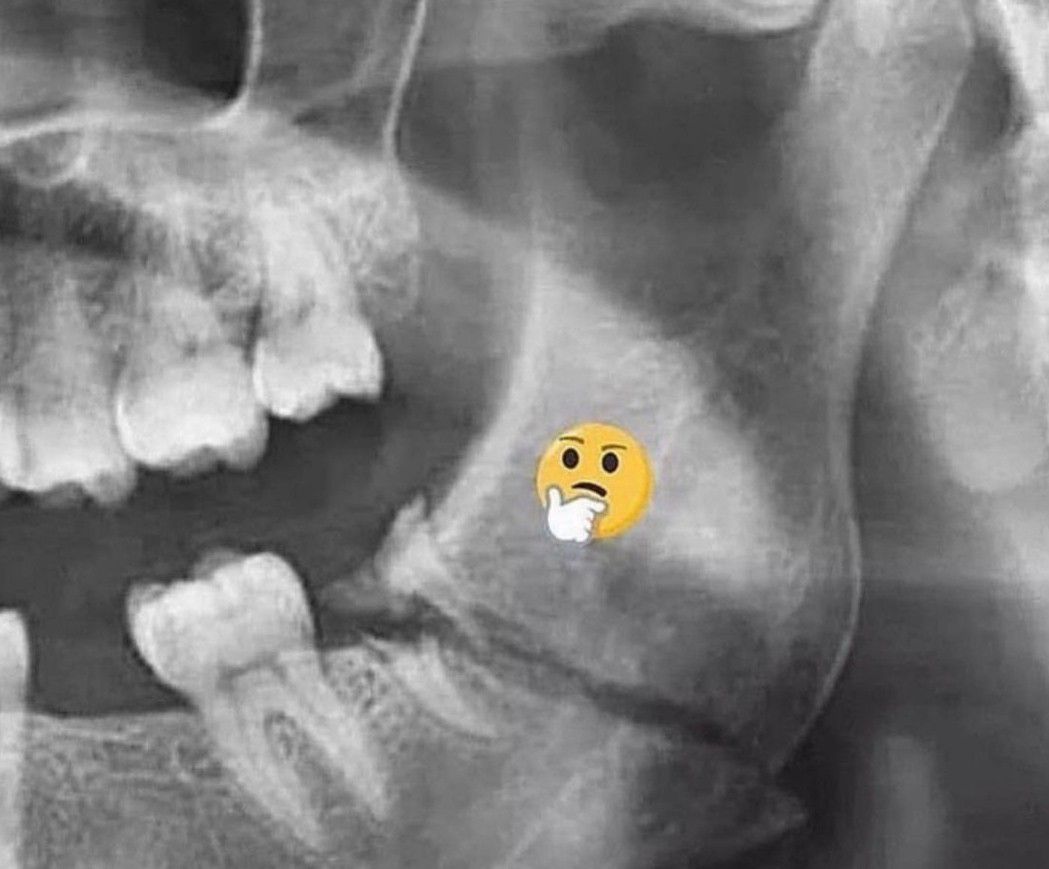

Treatment Approach

What will be the treatment approach?

Dentistry

Casestudy